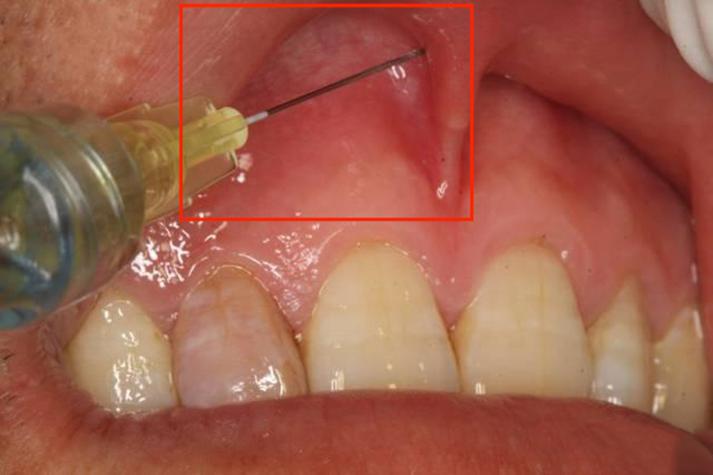

上颌前庭沟进针点

目标:麻醉上颌牙槽前神经(通常包括切牙孔)和上牙槽中神经。 进针区域:上颌尖牙牙根尖对应的区域,这是最经典、最常用的进针点。

定位标志:

- 上颌尖牙:找到上颌两侧“犬齿”,也就是尖尖的、比较长的牙齿。

- 颊侧牙龈:将患者的上嘴唇翻开,观察上颌尖牙对应的牙龈区域。

进针点“图片”:

- 想象一张口腔内侧面图,你能看到一排上牙。

- 将目光聚焦在最靠前的尖牙上。

- 沿着这颗尖牙的牙龈,向内侧(向脸颊方向)看,你会看到一个明显的凹陷,这就是上颌前庭沟。

- 进针点就位于这个沟里,大致在尖牙牙根尖所对应的正下方。

- 针尖的朝向:针头应沿着与牙长轴大约45度角的方向,刺入粘膜,然后改变角度,使其与牙长轴平行,继续向深处推进,直达骨面。